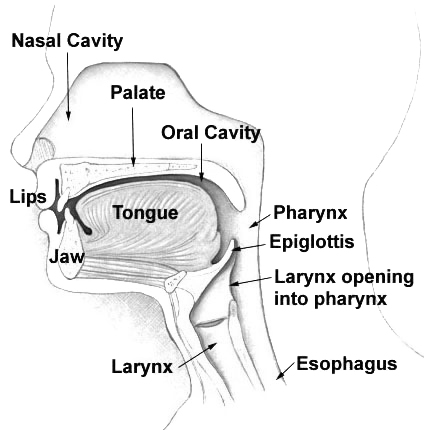

Nasal passage anatomy. Beyond the nasal valve the nasal passages are lined mostly by membranes more like the lining of the lungs called respiratory epithelium which is thin and rich in blood vessels. The sinuses are part of your nose and respiratory system. Openings into the nasal cavity.

In bones behind your nose are your sphenoid sinuses. Anatomy of the nasal cavity. This region is divided into a labyrinth of slit like passages by multiple bony proturbances that fill the nose and act as shelves.

The exhaled air travels in the reverse path and leaves the body through the nasal cavity. The superior the middle and the inferior turbinates. Theyre lined with soft pink tissue called mucosa.

During inhalation air enters through the nostrils and passes via the nasal cavity into the pharynx and larynx the next sections in the respiratory tract to eventually reach the lungs. Anatomy and physiology of the nasal cavity inner nose and mucosa introduction. Anatomy of the nose.

The external nose consists of paired nasal bones and upper and lower lateral cartilages. The nasal cavity refers to the interior of the nose. The nasal cavity is the most superior part of the respiratory tract.